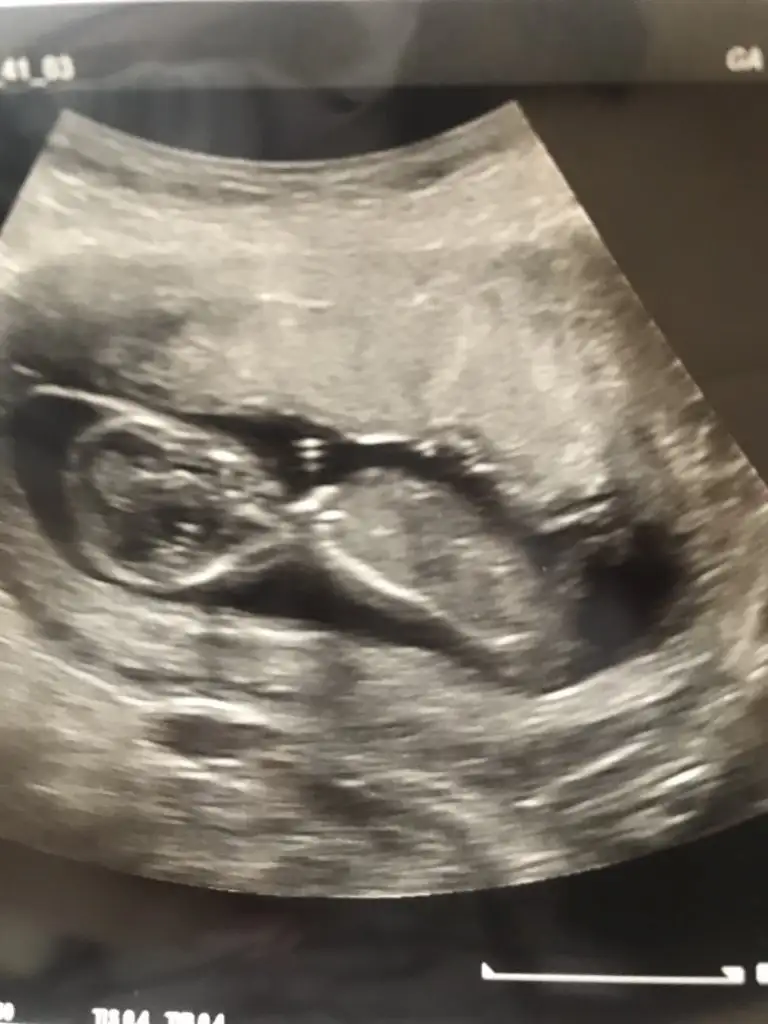

Karından bakıldı ise kız en iyi nub için 11 12 13 hafta paylaşınIkra meyra canım bakar mısın ilk fotoyu atmıstım daha önce ikinci foto 7. Haftadan

Canım ilk foto için karındansa erkek demiştin bende 7. Hafta fotosunu atayım dedim 10. Haftamda tekrar gideceğim o zaman yine atayımKarından bakıldı ise kız en iyi nub için 11 12 13 hafta paylaşın

Evet biliyorum ilkte erkrek demiştim kese konumu pek guven vermiyor o nedenle 11 12 13 hafta usg olursa paylalın 10 haftada değilde 11 haftada gitsenizCanım ilk foto için karındansa erkek demiştin bende 7. Hafta fotosunu atayım dedim 10. Haftamda tekrar gideceğim o zaman yine atayım

Hem net değil hemde 11 12 13 hafta olmalıBana da tahmin yapabilir misiniz 15+1 göstermedi cinsiyeti bugün bıcırık :)Ikra meyra

Mrb 13 haftalik olduk cok sukurKız gibi net de değil kız sanki 12-13 olunca tekrar usg paylaşın

bu da diger acidan fotografi ayagi kapatmis gibi amabu bu haftaki goruntusu 12. hafta gecen hafta erkek demistiniz ama emin olamamistiniz@ikrameyra